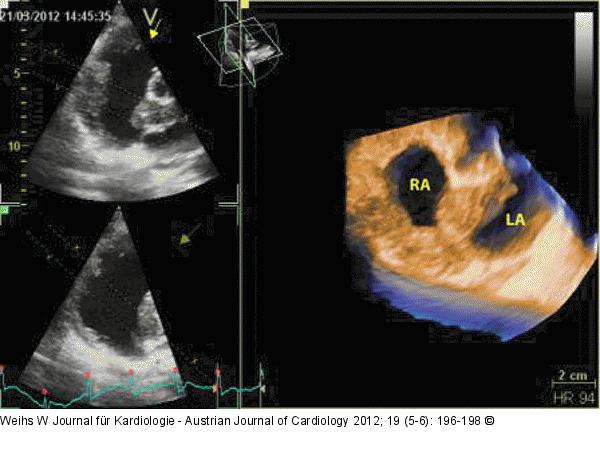

Abbildung 5: Echo Dreidimensionaler Schnitt durch die Raumforderung, welche den gesamten Vorhof umgibt. RA: rechter Vorhof; LA: linker Vorhof |

Dreidimensionaler Schnitt durch die Raumforderung, welche den gesamten Vorhof umgibt. RA: rechter Vorhof; LA: linker Vorhof |